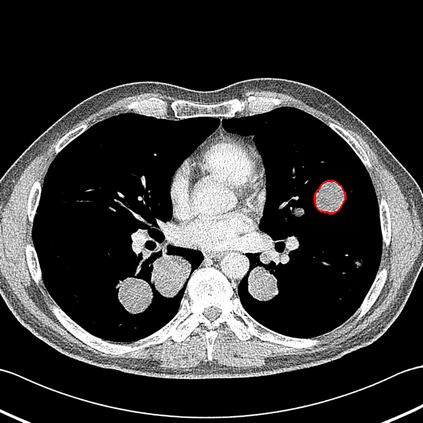

Radiomics uses quantitative medical imaging features to predict clinical outcomes. Currently, in a new clinical application, finding the optimal radiomics method out of the wide range of available options has to be done manually through a heuristic trial-and-error process. In this study we propose a framework for automatically optimizing the construction of radiomics workflows per application. To this end, we formulate radiomics as a modular workflow and include a large collection of common algorithms for each component. To optimize the workflow per application, we employ automated machine learning using a random search and ensembling. We evaluate our method in twelve different clinical applications, resulting in the following area under the curves: 1) liposarcoma (0.83); 2) desmoid-type fibromatosis (0.82); 3) primary liver tumors (0.80); 4) gastrointestinal stromal tumors (0.77); 5) colorectal liver metastases (0.61); 6) melanoma metastases (0.45); 7) hepatocellular carcinoma (0.75); 8) mesenteric fibrosis (0.80); 9) prostate cancer (0.72); 10) glioma (0.71); 11) Alzheimer's disease (0.87); and 12) head and neck cancer (0.84). We show that our framework has a competitive performance compared human experts, outperforms a radiomics baseline, and performs similar or superior to Bayesian optimization and more advanced ensemble approaches. Concluding, our method fully automatically optimizes the construction of radiomics workflows, thereby streamlining the search for radiomics biomarkers in new applications. To facilitate reproducibility and future research, we publicly release six datasets, the software implementation of our framework, and the code to reproduce this study.

翻译:放射科使用定量医学成像特征来预测临床结果。目前,在一个新的临床应用中,通过一个超常试验和高压过程,通过人工操作,从广泛的现有选项中找到最佳放射法。在本研究中,我们提议了一个框架,自动优化每个应用程序的放射工作流程的建设。为此,我们将放射作为模块工作流程,并包括每个部件的大量通用算法。为了优化每个应用程序的工作流程,我们使用随机搜索和聚合的自动机学习方法。我们用12种不同的临床应用来评估我们的方法,结果在曲线下应用的以下领域:1) 脂色瘤(0.83);2) 脱氧型纤维瘤(0.82);3 初级肝脏肿瘤(0.80);4 气肠肿瘤(0.77)、5 彩虹肝脏移植(0.61); 6 脑膜细胞变异常(0.45); 7) 肝细胞变异常(0.8) 脑纤维变异位(0.80); 9) 直径直线型癌症(0.74) 和头型癌症(0.77) 直径研究(10) 。